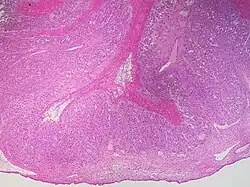

This type of functional cyst occurs after an egg has been released from a follicle. The follicle then becomes a secretory gland that is known as the corpus luteum. The ruptured follicle begins producing large quantities of estrogen and progesterone in preparation for conception. If a pregnancy doesn't occur, the corpus luteum usually breaks down and disappears. It may, however, fill with fluid or blood, causing the corpus luteum to expand into a cyst, and stay in the ovary. Usually, this cyst is on only one side, and does not produce any symptoms.[1][2]

In women of reproductive age, cysts with a diameter of less than 5 cm (2.0 in) are common, clinically inconsequential, and almost always a physiological condition rather than cancer or another medical condition.[3] In postmenopausal women the threshold for concern is 1 cm (0.39 in).[3] Although ovarian cancer may be cystic, it does not arise from benign corpus luteum cysts.[3] Medical specialty professional organizations recommend no follow-up imaging for cysts which are considered clinically inconsequential.[3]